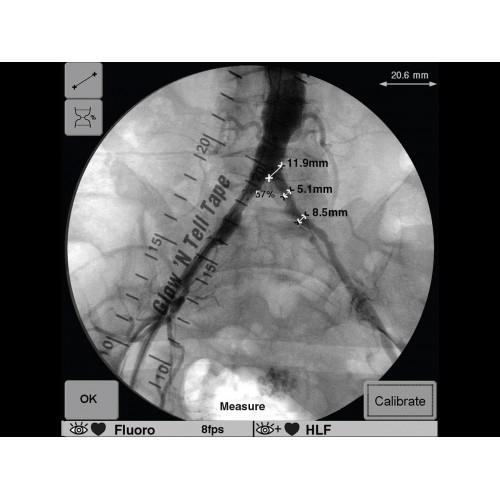

Инновационная мобильная С-дуговая система для интраоперационной визуализации с высоким разрешением. Обеспечивает хирургов качественным изображением в реальном времени при минимальной лучевой нагрузке. Усовершенствованная эргономика позволяет легко позиционировать аппарат в условиях операционной. Поддерживает интеграцию с современными хирургическими навигационными системами.

Передовая рентгенохирургическая система GE OEC 9900 Elite представляет собой инновационное решение для проведения широкого спектра малоинвазивных вмешательств. Это оборудование премиум-класса сочетает высочайшее качество визуализации с интуитивно понятным управлением, устанавливая новые стандарты в области интраоперационной рентгеноскопии.

GE OEC 9900 Elite оснащен революционной системой визуализации, обеспечивающей кристально четкое изображение анатомических структур. Интеллектуальная система автоматически адаптирует параметры исследования под конкретную хирургическую задачу, обеспечивая оптимальный баланс между качеством изображения и лучевой нагрузкой. Особое внимание уделено удобству работы операционной бригады.

В операционной практике GE OEC 9900 Elite демонстрирует исключительную эффективность при проведении сложных малоинвазивных процедур. Оборудование позволяет значительно сократить время вмешательства и повысить его безопасность для пациента. Многие хирурги отмечают улучшение точности операций и комфорт работы с системой.

В ведущих медицинских центрах GE OEC 9900 Elite успешно применяется для проведения сложных кардиологических, нейрохирургических и ортопедических вмешательств. Система доказала свою эффективность при выполнении стентирования коронарных артерий, эмболизации сосудов головного мозга и вертебропластики. Многие учреждения отмечают повышение качества операций после внедрения этого оборудования.